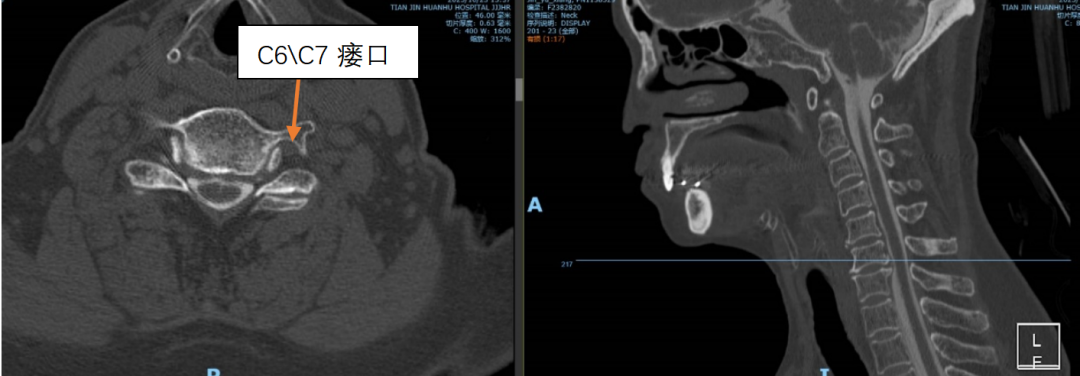

为精准定位“漏点”,刘伟主任医疗团队为靳女士安排了腰椎穿刺测压和全脊柱核磁水成像检查。结果证实了诊断:颅压低至68mmH₂O(正常约为80-180mmH₂O),进一步行腰大池CT造影剂清晰地显示,漏口就隐藏在颈7/胸1和胸1/2这两个节段。

术前术后影像对比

术前影像